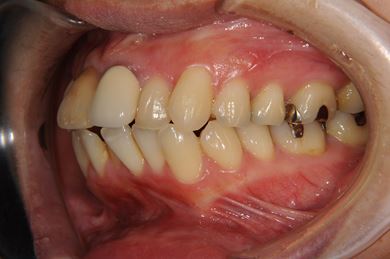

全顎矯正治療+セラミック治療

| 性別/年齢 | 女性 / 35歳 | ||||||||||||||||||||||||||||||||

| 主訴 | 出っ歯 上顎前歯の並び | ||||||||||||||||||||||||||||||||

| 治療方針 | 上下歯牙がだいぶ前にでていて口が閉じづらい状態でした。なるべく金属が入っている歯を抜歯したいので、上下左右第二小臼歯を抜歯して、その隙間を利用して、口元をさげていきました。また、口元を最善の状態にうるために、抜歯スペースを使用したあと、上下左右のインプラントアンカー(釘)でより一層口元を後ろにさげていきました。ただの抜歯ケースよりだいぶ口元が下がっているのが分かります。抜歯したスペースががたつき(叢生量)で使用してしまう場合には、このような方法でより口元をさげることができます。お顔立ちがとてもよくなりました。とても協力していただけたので、しっかりと良くなることができました。 | ||||||||||||||||||||||||||||||||

| 治療内容 | 唇側矯正(ホワイト・上下左右第二小臼歯抜歯・上下インプラントアンカー)、オールセラミッククラウン1本(オールセラミック用土台1本)、ジルコニアフレームオールセラミッククラウン1本 | ||||||||||||||||||||||||||||||||